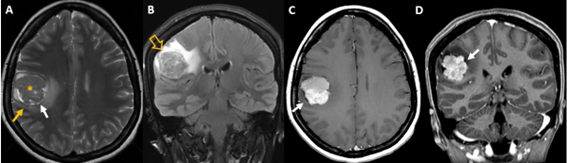

Figura 2. Imagen A corte transversal potenciado en T2 FSE, imagen B FLAIR coronal, imagen C T1 SE e imagen D reconstrucción coronal de secuencia 3D T1 gradiente tras administración de contraste.

Hallazgos: Lesión isointensa al córtex cerebral localizada en zona subcortical anterior del lóbulo parietal derecho (*) con LCR separando su borde medial del parénquima adyacente (flechas blancas en A, C y D), correspondiente a signo de la hendidura de LCR. También se observan zonas de desplazamiento de sustancia gris sin expansión de sustancia blanca (flecha naranja en A). Estos hallazgos son indicativos de lesión extraaxial. No obstante, en secuencia FLAIR la lesión está casi completamente rodeada de edema vasogénico (flecha hueca en B) y tras la administración de contraste se visualiza captación intensa de contraste sin lograr demostrar conexión meníngea (ausencia de cola dural en imágenes C y D).